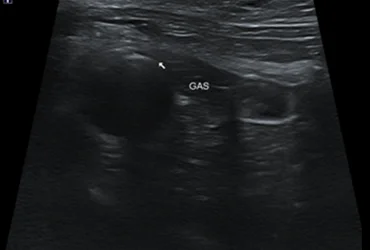

1. 복부 초음파 검사

간, 담낭, 췌장, 위장관 등의 구조적 이상을 평가하여 질환의 유무를 확인합니다. 실시간 영상으로 장기의 형태, 크기, 내부 구조를 정밀하게 모니터링합니다.

비침습적이고 안전하게 소화기계 문제를 스크리닝하고 진단합니다.

• 급성 황달 증상을 보인 반려묘,복부 초음파 및 혈액검사로 담도계 질환

진단 후 신속한 처치로 회복

갑작스러운 황달과 식욕부진으로 내원한 XXX(환자명)은 응급 검사를 통해 담도계의 심각한 문제를 확인하였습니다.

즉각적인 내과적 처치 및 필요한 경우 외과와의 협진을 통해 위험한 고비를 넘기고 건강을 되찾았습니다.